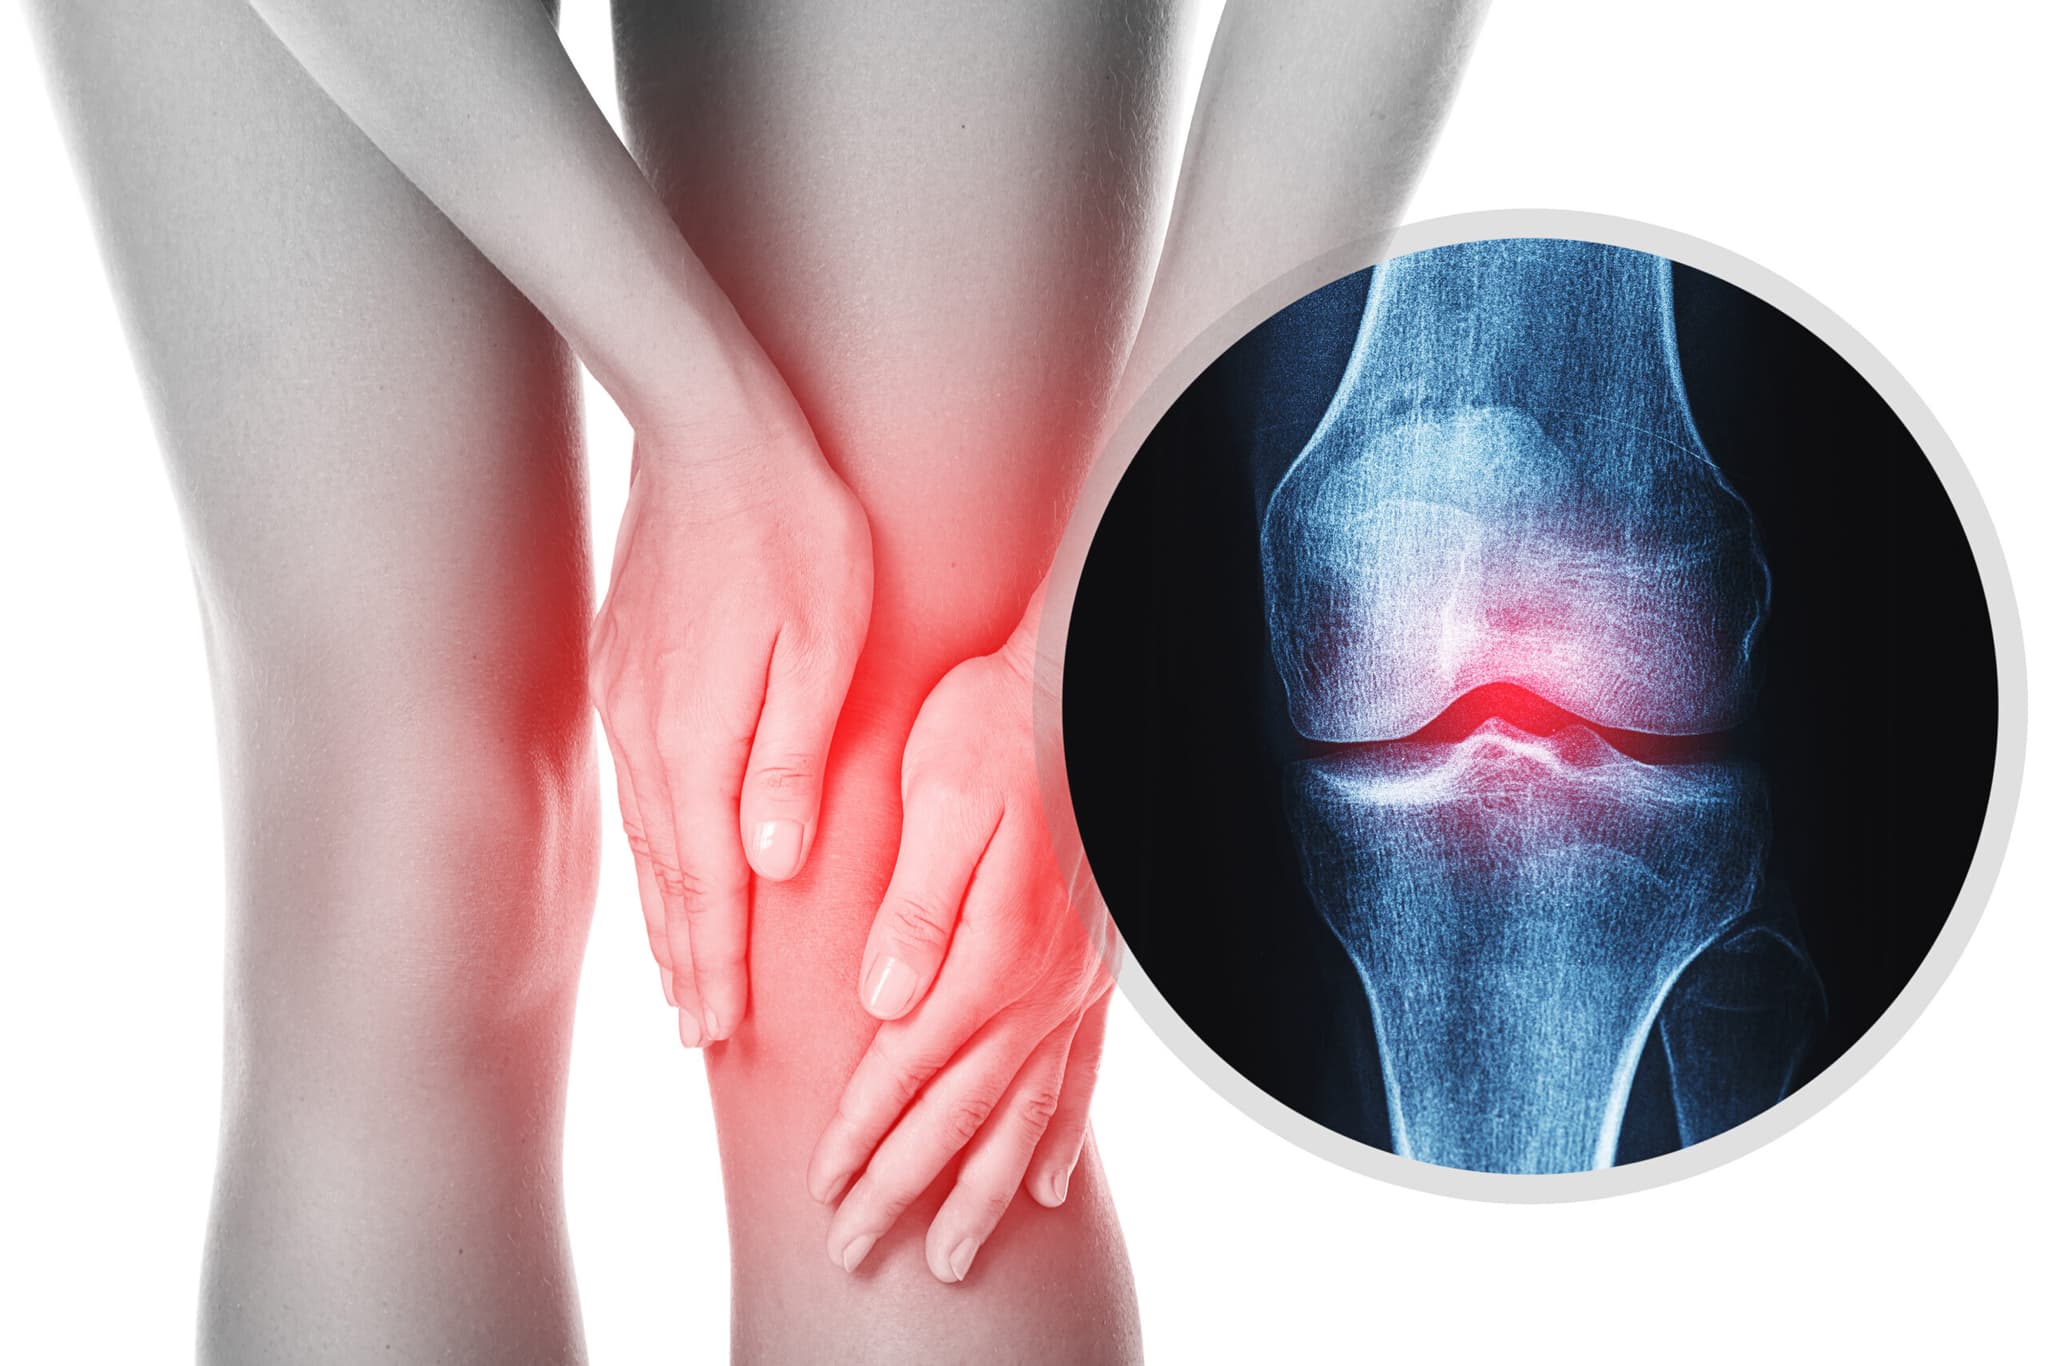

Is Your Joint Pain Osteoarthritis or Rheumatoid Arthritis?

Understand the true source of your knee pain. Read the article to learn the differences between osteoarthritis and rheumatoid arthritis, and manage your health consciously.

Knee pain is one of the most common complaints encountered in orthopedic practice. However, its underlying cause is often misunderstood. The terms “osteoarthritis” and “rheumatism” are frequently used interchangeably, even though they represent entirely different biological processes.

Osteoarthritis is a degenerative joint disease characterized by the gradual breakdown and deterioration of articular cartilage.

-The protective cushioning between joint surfaces diminishes

-Structural changes occur in the bone

-Joint mobility may become limited